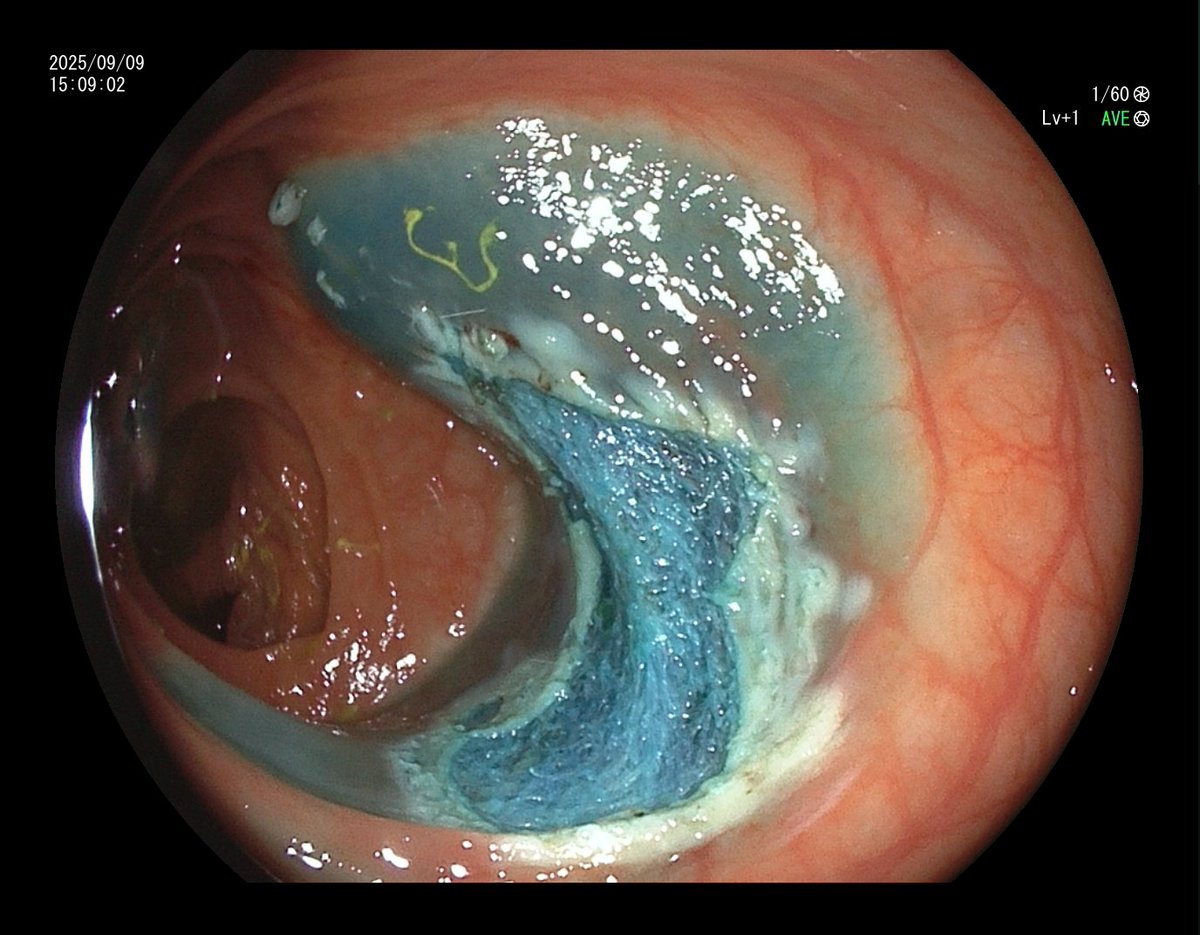

1. Antrum, low grade dysplasia. Removed via ESD. Specimen 43x32mm / dysplasia 20x13mm. R0